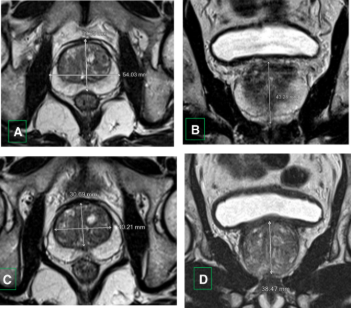

Gambar 1. Gambaran prostat yang membesar di MRI

- Penilaian ukuran prostat, menggunakan MRI atau TRUS (ultrasonografi transrektal).

Pemeriksaan ini penting karena ThuFLEP hanya dapat dilakukan bila tidak ditemukan tanda kanker prostat aktif. Dengan evaluasi menyeluruh, dokter dapat memastikan bahwa prosedur laser ini menjadi pilihan paling aman dan efektif untuk pasien.